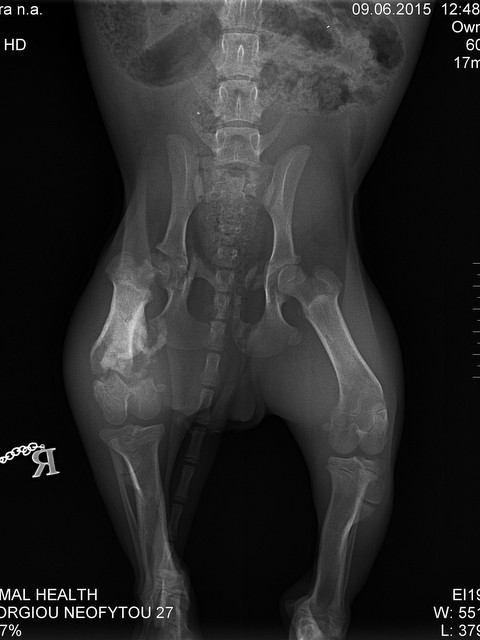

Die ebenfalls noch sehr junge TYRA - sie hat ein gebrochenes Beinchen und die rechte Hüfte ist gebrochen, das Beinchen wurde bereits auf Zypern versorgt, doch die Hüfte muss noch operiert werden. Tyra hat ihr liebevolles Zuhause zwar schon gefunden, aber wir wollen diese Operationskosten auf jeden Fall gerne übernehmen.